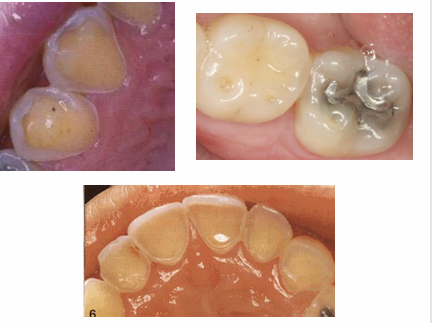

signs of enamel erosion

-broad concavities on cusp tips (mandibular molars)

-smooth silky glazed appearance

-increased incisal translucency

-”raised” amalgam restorations (enamel wears away but amalgam does not)

-loss of surface anatomy in young children

-hypersensitivity